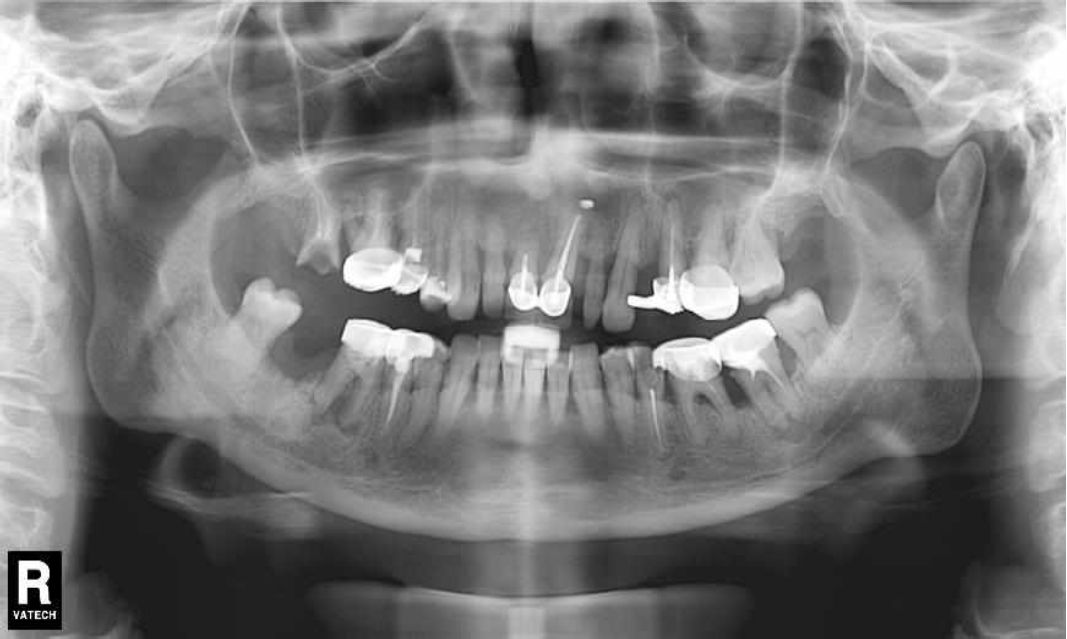

За пародонтологическим лечением обратилась женщина 61 года с жалобами на неприятный запах из полости рта, кровоточивость десен при чистке зубов, подвижность зубов, несостоятельность ортопедических конструкций.

Ранее у пародонтолога не наблюдалась. При осмотре выявлены: неудовлетворительная индивидуальная гигиена полости рта, пародонтальные карманы до 7 мм, обильная кровоточивость и гноетечение из пародонтальных карманов, подвижность зубов 4.2, 4.1, 3.1, 3.2 II степени, обильные над- и поддесневые зубные отложения (рис. 1). На ортопантомограме отмечается резорбция костной ткани до ½ длины корня, очаги остеопороза (рис. 2). Пациенту был поставлен диагноз хронический генерализованный пародонтит тяжелой степени тяжести. При осмотре была составлена пародонтограмма с использованием компьютерного зондирования (рис. 3).

Рис. 1. Внешний вид

Через 6 месяцев при осмотре выявлен удовлетворительный уровень индивидуальной гигиены, отсутствие участков кровоточивости и гноетечения (рис. 4), пародонтальные карманы уменьшились в размерах (рис. 5). Пациент отмечает значительные улучшения. После стабилизации пародонтологического статуса пациент направлен для дальнейшего ортопедического лечения.

Рис. 4. Динамика результата через 6 месяцев